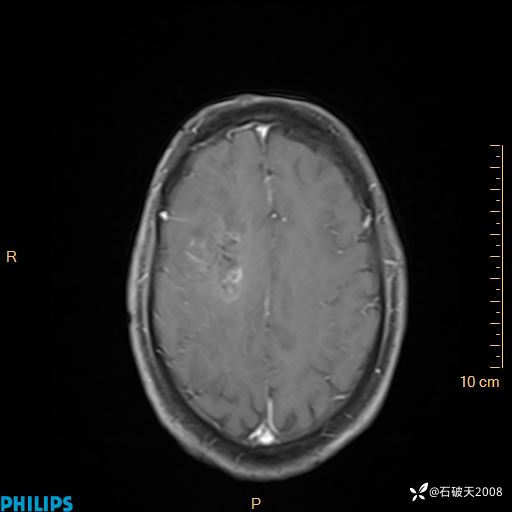

2024.2.21MR

增强轴位